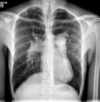

RN a termo.

Cardiomegalia massiva em um neonato com pulmão normal (sem edema alveolar ou intersticial, sem derrame pleural)

Cardiomiopatia neonatal.